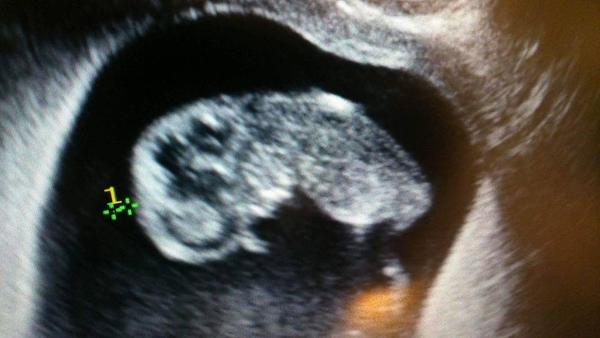

@ariana195195 Jeej malé mimi ako si spinka 🤗 len tak ďalej, prajem veľa zdravička ☺